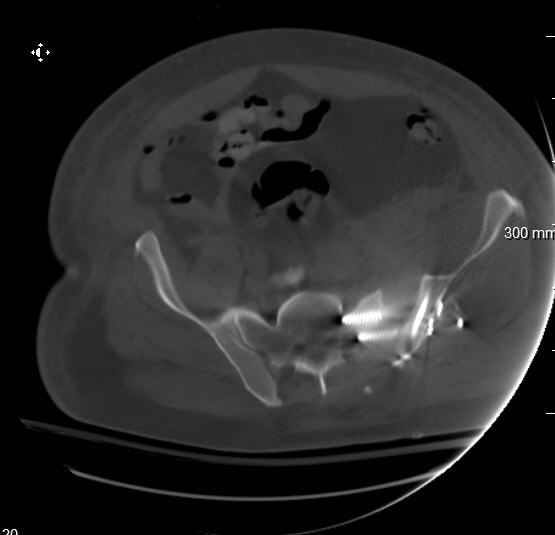

Hello gentlemen- Case is 52 YO male, fell out of treestand while deerhunting. He is 6 ft, approx. 260-275 lbs. Was hemodynamic unstable at local ER, sent to our Trauma center where circumferential pelvic binder placed and pt. stabilized with fluid, blood, and rewarming. Angiography not performed. An extraperitoneal bladder disruption was found, uro elected to treat non-operatively. Initial xray (not shown) demonstrated 5-7 cm wide at symphysis and SI joint. The first image attached is of CT once binder is in place. On post trauma day 5 the pt was taken to OR for ORIF of his iliac wing fracture and SI dislocation. The swelling/3rd spacing of fluid in the area of symphysis was profound, but quite acceptable posteriorly. Patient was prone for procedure, as I thought too difficult to fix the wing in lateral position. Of course the repair of wing was easy, but reduction of SI very demanding. The Floro images document the residual lack of reduction. That was the closest I could get it using 6mm joystick in wing, and clamp on sacrum and clamp through notch. The fixation was (initially) rigid. Anterior ex fix with supra-acetabular pins was placed due to condition of soft tissues, massive "beer-belly" overhanging the crest. Post trauma day ten patient's xray shows failure of posterior construct. Plan was to perform revision orif once soft tissues resolve considerably for full anrterior fixation and posterior fixation. However, while Im away for holiday (on Post trauma day 15), pt is developing septic clinical appearance, and trauma suspects pelvic abcess near symphysis and performs I and D - finds nothing but no primary closure performed. Posterior tissues/incision continue to look healthy. Now is post trauma day 17, pt is still tubed/on dopamine/and wbc still elevated, anterior incision still packed open. Clearly must get to bottom of possible sepsis, but then what? Thanks for you time - sorry for such lengthy clinical description. Thomas Schaller Kalamazoo, Michigan

Request for more images.. Axial and coronal recon (pt in binder.)

9. At this point, (if he's alive) get busy get a CT so you can understand what's happened, where the implants were, what fixation zones remain, remove the failed posterior implants, turn him supine, expose the symphysis and SI joint, reduce and clamp them both, fix them according to the CT info, close the wounds if clean, pack open if not, get another CT to assure adequate reductions and implant safety, treat his wound culture results with appropriate antibiotics, and nourish him.